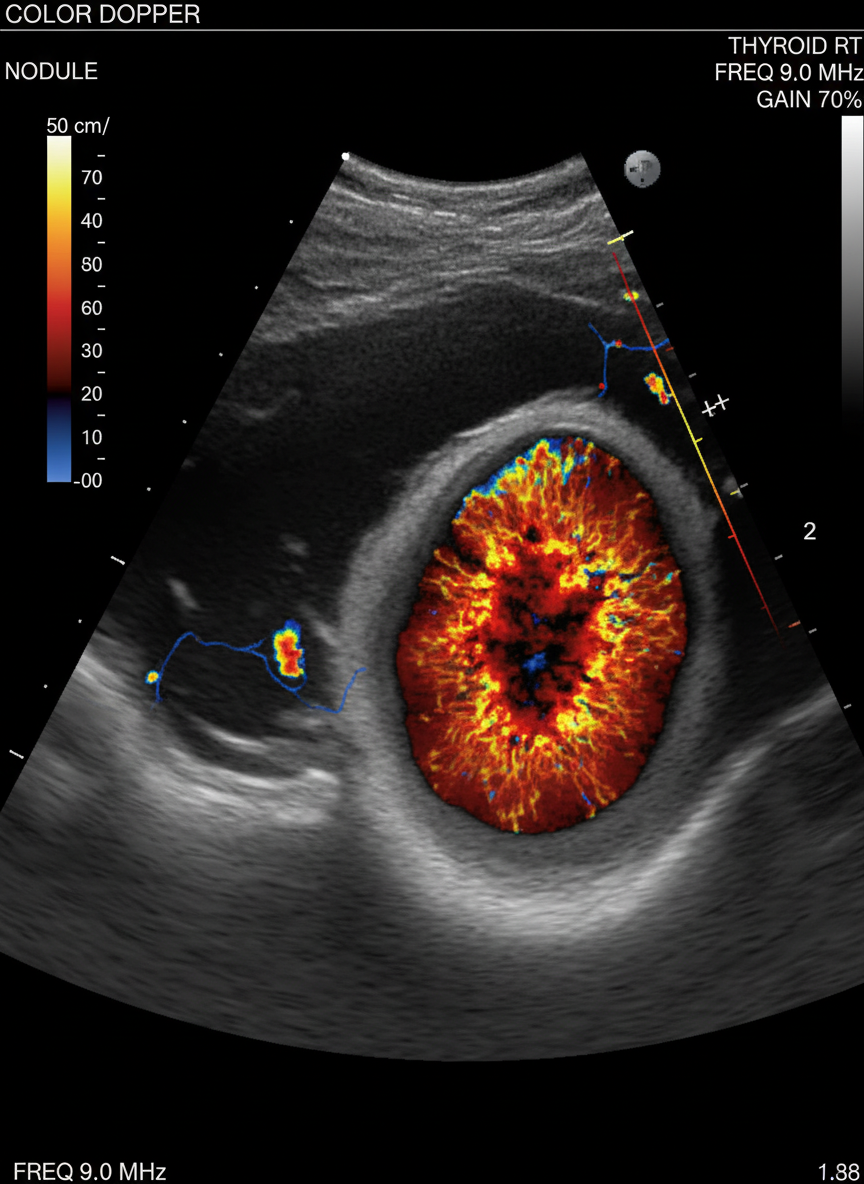

- 갑상선 초음파: 갑상선 내부의 결절 유무, 크기, 모양, 경계 등을 아주 자세히 확인할 수 있는 검사예요.비교적 간단하고 통증 없이 진행돼서 많이 사용된답니다.암이 의심되는 결절이 발견되면 다음 단계로 넘어가죠.